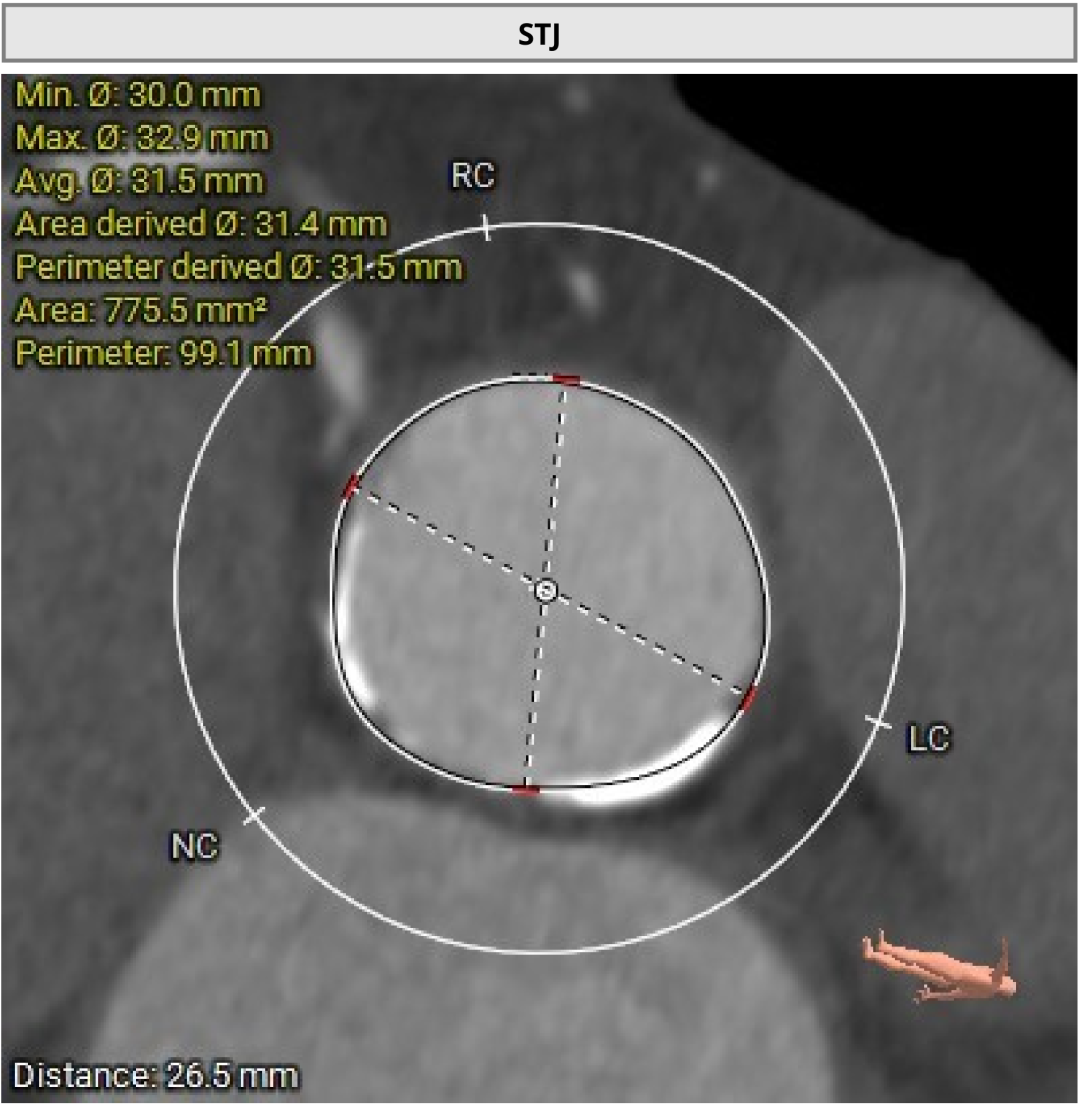

进一步评估显示,患者瓣膜狭窄程度重,瓣叶钙化明显,左心室腔径偏小,手术中对器械通过、瓣膜释放以及循环稳定性的要求都更高。团队结合术前影像和整体身体状况,制定了周密的介入治疗方案,并做好相关风险预案。

CT评估

瓣膜评估